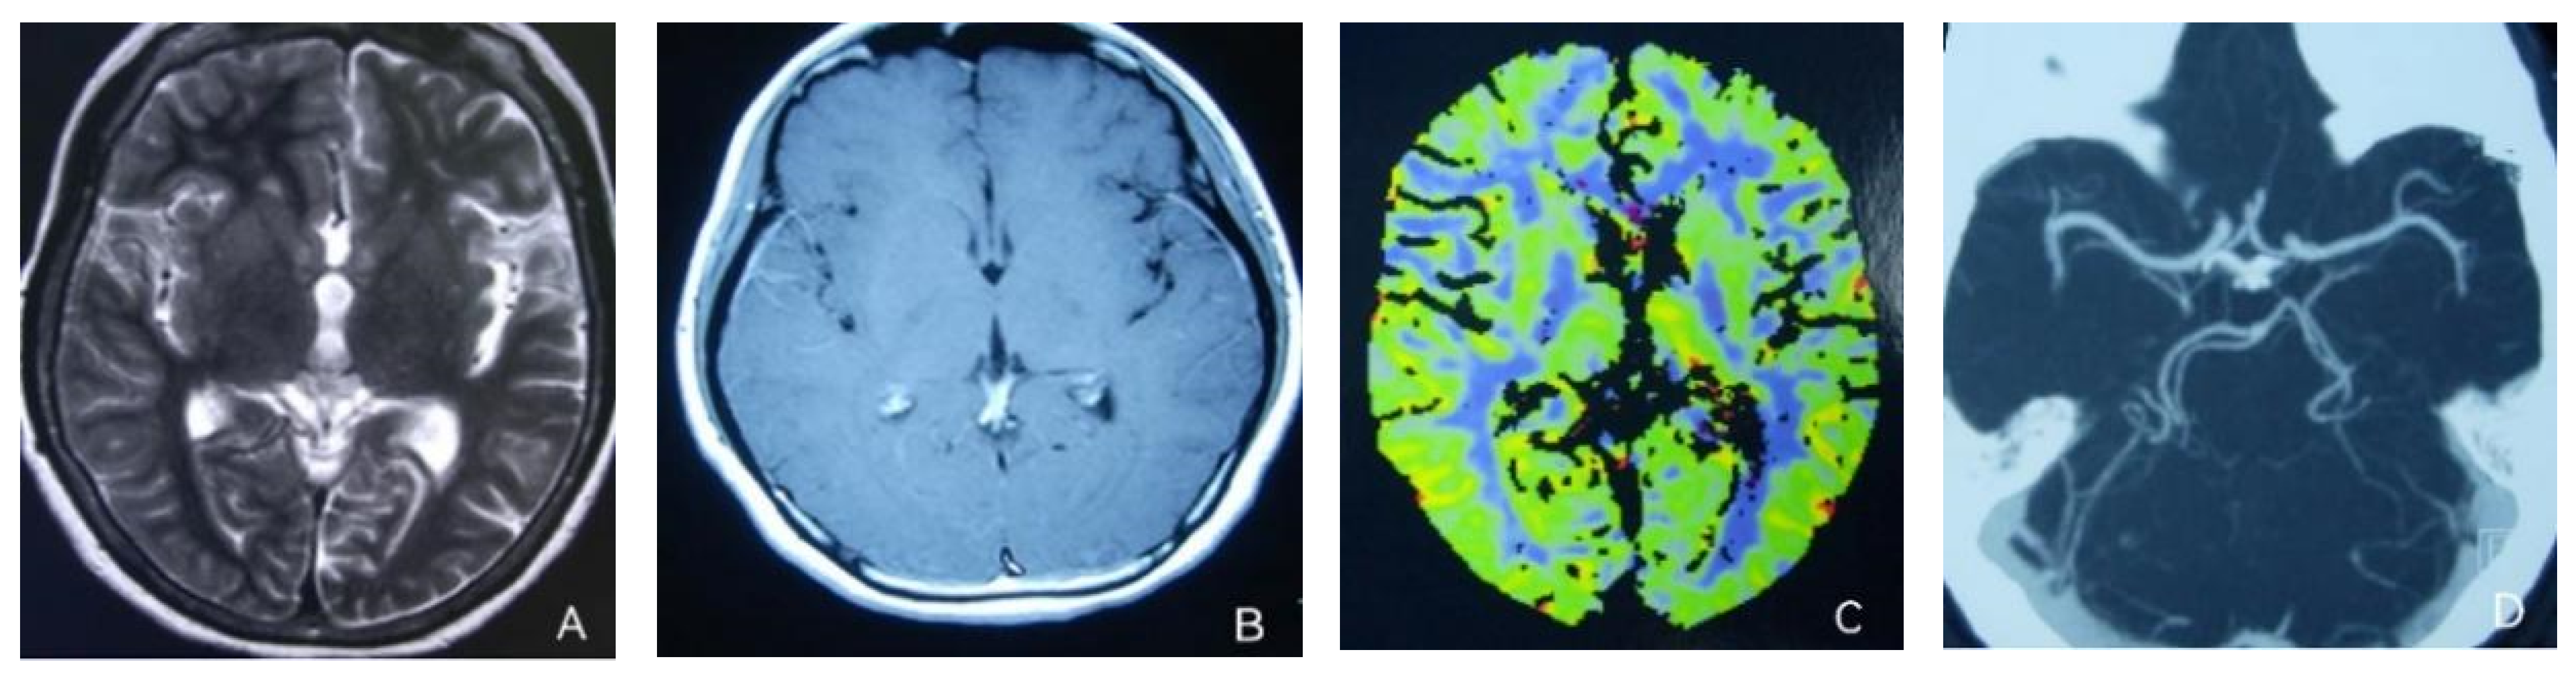

2. Case Presentation

- Iizuka, T.; Tominaga, N.; Kaneko, J.; Sato, M.; Akutsu, T.; Hamada, J.; Sakai, F.; Nishiyama, K. Biphasic neurovascular changes in prolonged migraine aura in familial hemiplegic migraine type 2. J. Neurol. Neurosurg. Psychiatry 2015, 86, 344–353. [Google Scholar] [CrossRef] [PubMed]